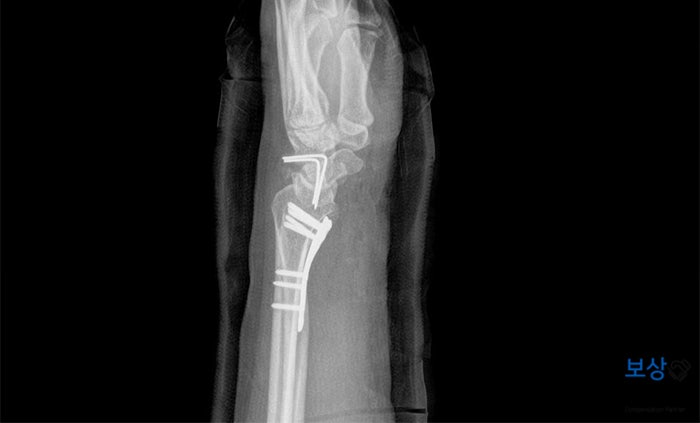

확실한 골 유합을 위해서 상처 부위를 절개하여 금속판과 나사, 그리고 금속 핀을 사용하여 골절된 뼈들을 단단하게 고정시켰습니다. (금속판 내고정술, 골이식술, 경피적 핀고정술)